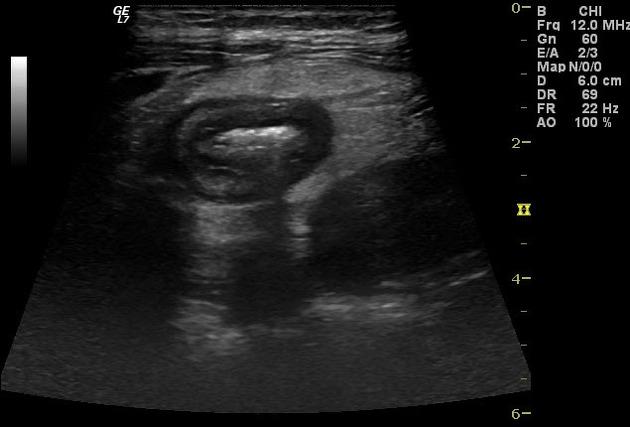

dilate .Aspect echographie percutanee

du colon dans maladie de Crohn est image epaissisement de la

parietale du colon et image de complication abcesde de la

paroi du colon .

Aspect ecographique une abces entre deux anses du

grele dans une maladie de Crohn . En haute de

frequence on peut voyait image de epaissisement de

la paroi du colon ou ileon terminale . |